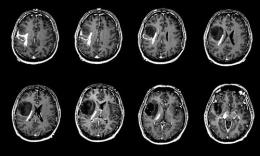

پزشکی را که عمدتاً بر درمان عارضههای ستون فقرات متمرکز میگردد، دکتر متخصص ستون فقرات مینامند. متخصص طب فیزیکی و توانبخشی، متخصص کایروپراکتیک، دکتر فیزیوتراپی، جراح ارتوپد، جراح عصب، متخصص مدیریت درد، متخصص بیهوشی و روماتولوژیست و متخصص مغز و اعصاب برای رفع این گونه عارضهها به کمک بیماران میآیند. مناسبترین و بهترین دکتر متخصص ستون فقرات و یا گروهی از متخصصین با توجه به ماهیت، شدت و مدت بروز علائم انتخاب میشود.